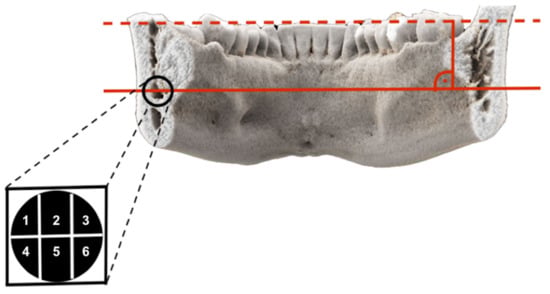

| Second Molar | Segment 1 | Segment 2 | Segment 3 | Segment 4 | Segment 5 | Segment 6 |

|---|---|---|---|---|---|---|

| Generally Yes | 66.7% | 94.4% | 61% | 75% | 91.6% | 61.1% |

| If Segment 1 Yes | - | 95.8% | 62.5% | 95.8% | 95.8% | 58.3% |

| If Segment 2 Yes | 67.6% | - | 73.5% | 73.5% | 88.2% | 64.7% |

| If Segment 3 Yes | 63.6% | 100% | - | 72.7% | 90.9% | 81.8% |

| If Segment 4 Yes | 85.2% | 96.3% | 59.3% | - | 96.3% | 66.7% |

| If Segment 5 Yes | 66.7% | 90.9% | 63.6% | 75.8% | - | 66.7% |

| If Segment 6 Yes | 68.2% | 100% | 81% | 77.3% | 100% | - |